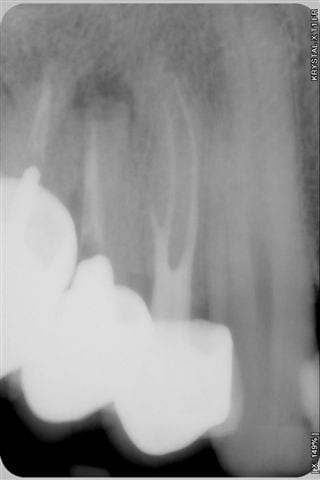

patient reçu un mardi soir en urgence, se plaint d'une voussure persistante et douleureuse en regard de la 15 couronnée en céramique depuis une dizaine d'année.

ce patient a consulté,6 jours plus tôt un autre cabinet dont le titulaire n'a fait que lui donner des AB et un rendez vous à 3 mois!!!

Sur le poste d'où j'écris, je ne peux pas insérer de pièces jointes va savoir pourquoi? Je joindrai donc plus tard d'un autre poste, la radio prise le mardi ainsi que les radios pré et post opératoires du vendredi.

(à ta décharge l'endo m'a l'air belle et l'obturation par dessus a été rapide)

Pas celles avec une pathologie apicale à la radio. Faut te tenir au courant, ça m'éviterait de répondre des évidences alors que j'ai eu une dure journée (ça se sent sur le ton de mon premier message, non?)...

je ne critique absolument pas ce qui a ete fait, mais comment savoir que le retraitement va donner satisfaction? la lésion est peut être due a un sous traitement mais aussi bien a une anatomie canalaire particulière ou d'autres causes et meme si l'image radio semble bonne je pense que 2 mois sous provisoire afin d'objectiver radiologiquement une réussite de la réobturation aurait été plus sécurisant.